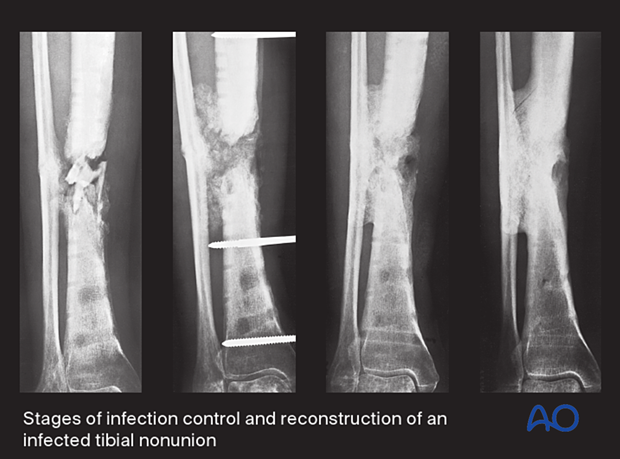

This patient had an acute fracture, necessitating internal fixation. However, a late infection occurred. X-rays and subsequent debridement revealed an ununited fracture with minimal callus formation. Intercalary necrotic bone was debrided. The fracture was stabilized with an external fixator.

Appropriate antibiotics were administered. Bone graft was then placed in the fracture defect and between the tibia and fibula above and below the fracture. This combination of treatments improved both the biology and stability of the atrophic nonunion. Delayed healing occurred with a satisfactory outcome.